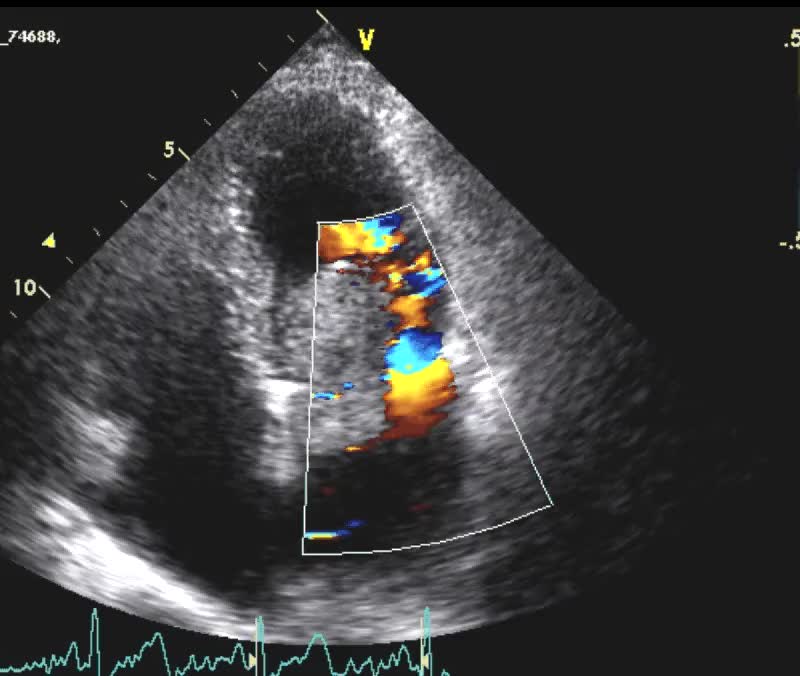

Botallo pervio

Andrea Barbieri